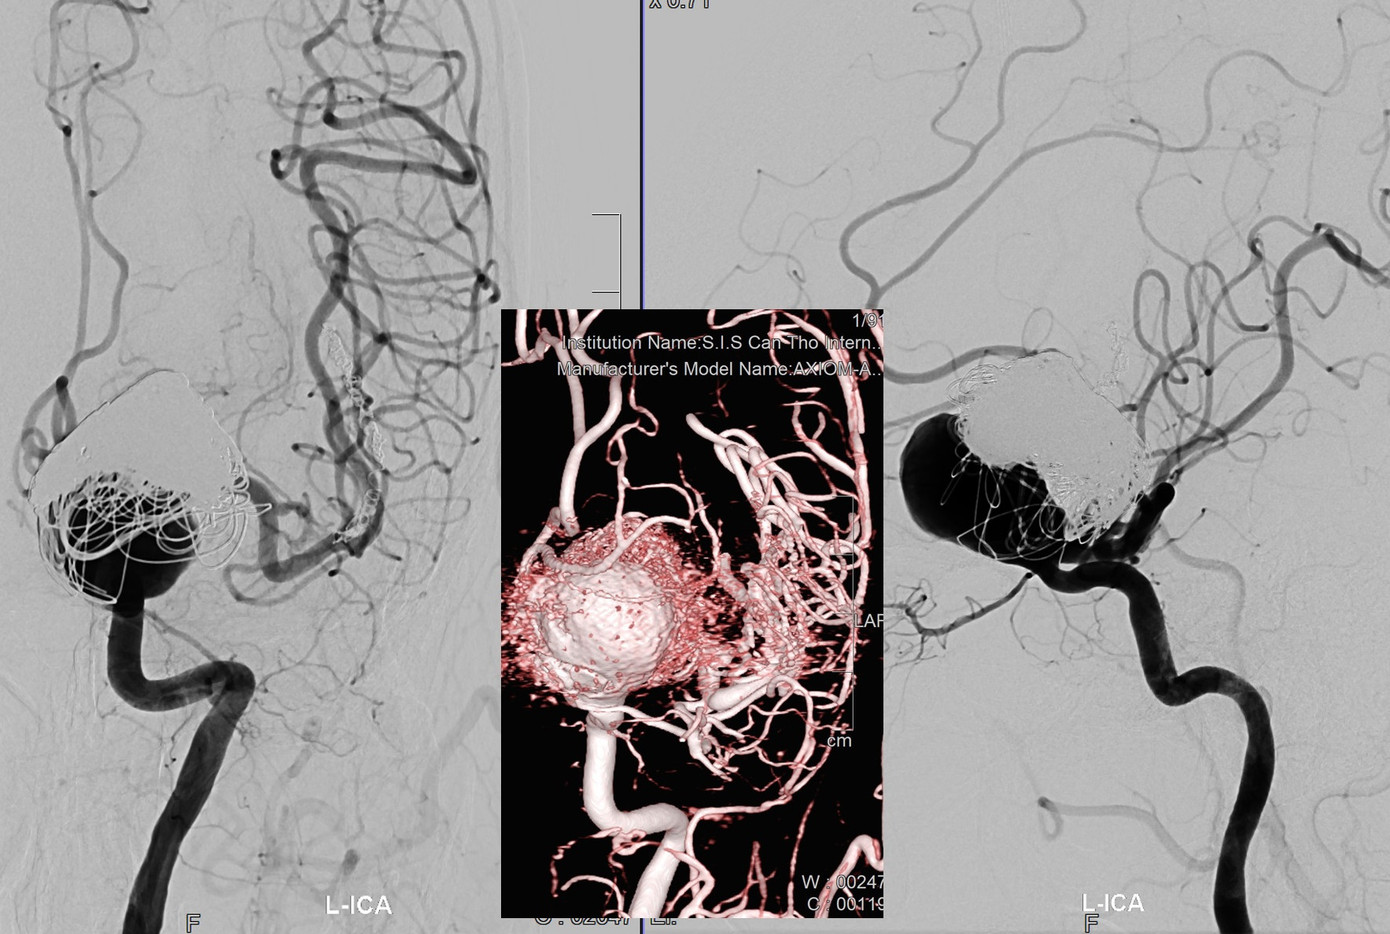

Qua thăm khám, kiểm tra hình ảnh, các bác sĩ phát hiện bệnh nhân có túi phình mạch máu não rất lớn kích thước 25mm x 35mm. Khai thác bệnh sử của bác sĩ từ phía người bệnh ghi nhận, bà S. từng 2 lần can thiệp túi phình tại một bệnh viện ở TPHCM và đã tiêu tốn gần 1 tỷ đồng. Tuy nhiên, sau 8 năm túi phình lại tái phát.

| Túi phình khổng lồ trong não nguy cơ vỡ khiến bệnh nhân tử vong bất kỳ lúc nào |

Kết quả kiểm tra hình ảnh chuyên sâu cho thấy túi phình nằm ở vị trí động mạch cảnh trong bên trái. Đây là đoạn động mạch mắt, bệnh nhân đã đặt coil một phần ở vị trí này. Các bác sĩ đã hội chẩn và đưa ra phương án điều trị duy nhất để cứu sinh mạng người bệnh là đặt stent chuyển dòng (FD). Phương pháp này sẽ thay đổi dòng chảy của máu không xoáy vào lòng túi phình, từ đó ngăn chặn nguy cơ vỡ túi phình.

TS.BS Trần Chí Cường cho biết, đây là một trường hợp phình mạch máu não khổng lồ rất khó. Vị trí túi phình nằm ở sâu trong não (động mạch cảnh trong đoạn động mạch mắt), cổ túi phình lại gập góc như “cua cùi chỏ” nên dây dẫn rất khó tiếp cận và đi ngang qua, đây là thách thức rất lớn cho ê kíp can thiệp. Sau gần 3 giờ, ca can thiệp với sự hỗ trợ của hệ thống máy DSA, công nghệ dựng hình 3D các bác sĩ đã đặt thành công Stent chuyển dòng cho người bệnh. Đây là ca túi phình khó nhất trong năm 2023.